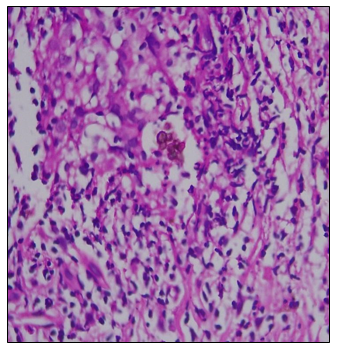

Histopathological examination revealed pseudoepitheliomatous hyperplasia, suppurative granuloma with epithelioid cells, multinucleated Langhans giant cells, lymphohistiocytic infiltrate, and the presence of sclerotic (Medlar) bodies on hematoxylin and eosin staining.

Figure 12 Histopathological features showing pseudoepitheliomatous hyperplasia and suppurative granulomas with Medlar bodies

Figure 13 Medlar bodies on HPE

A triad of pseudoepitheliomatous hyperplasia, noticeable neutrophilicinfiltration with the development of microabscesses, and distinctive sclerotic bodies is very specific for chromoblastomycosis.

Histopathology was key to diagnosis in all cases, consistently showing Pseudoepitheliomatous hyperplasia, Suppurative granulomas, Langhans giant cells. Most crucially, presence of sclerotic (Medlar) bodies, pathognomonic of chromoblastomycosis.